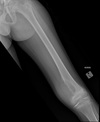

Perfectly

Aggressive in kid = OLEO 1. Osteomyelitis 2. Ewing sarcoma (diaphyseal) 3. Osteosarcoma 4. Lymphoma